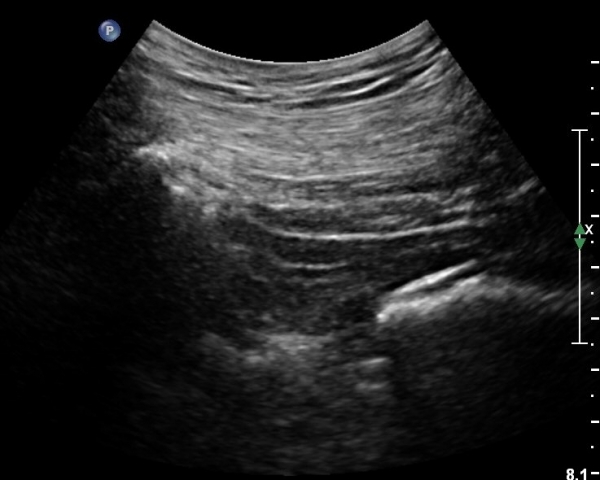

ÈÄ»óÀå°ñ±Ø ¿ÜÃø¿¡ ŽÃÊÀÚ¸¦ ¼öÆòÀ¸·Î ´ë¸é ½ÉÃþÀ¸·Î Àå°ñÀÌ °üÂûµÇ°í Àå°ñ Ç¥Ãþ¿¡ ´ëµÐ±Ù°ú ÁߵбÙÀÌ °üÂûµÈ´Ù(»çÁø 1).

ŽÃÍÀÚ¸¦ ´Ù¸®ÂÊÀ¸·Î ¼öÆò À̵¿ÇÏ¸é ½ÉÃþ¿¡¼­ Àå°ñÀÌ »ç¶óÁö°í »õ·Î¿î ±ÙÀ°ÃþÀÌ º¸À̴µ¥ À̰ÍÀÌ ÀÌ»ó±ÙÀ̰í ÀÌ»ç±Ù ½ÉÃþ¿¡¼­ Á°ñ½Å°æ¸£ °üÂûÇÒ ¼ö ÀÖ´Ù(»çÁø 2, 3).